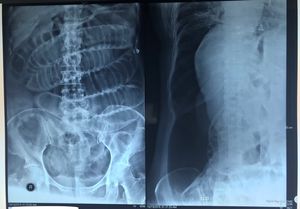

A 60-years old woman came to ED with abdominal pain. She had been experiencing abdominal pain, nausea, vomiting, abdominal distention, decreased stool and flatus in the past 3 days. Diagnosis?

The x ray is not suggesting any obstruction but her symptoms should match with obstruction at her age.

What are abnormal abdominal X-ray findings on that patient? What should be found on the X-ray in this case? Thank you